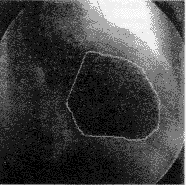

图3显示了本文基于自适应方向滤波所得到的左心室轮廓,图像分辨率为1024×1024×10bits。初始脊点数均为4。

(a)ED

(b)ES

图 3 ADF得到的左心室轮廓(a)和(b)为左心室的ED(舒张末期)和ES(收缩末期)